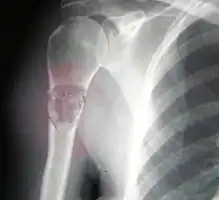

Telangiectactic osteosarcoma of the humerus